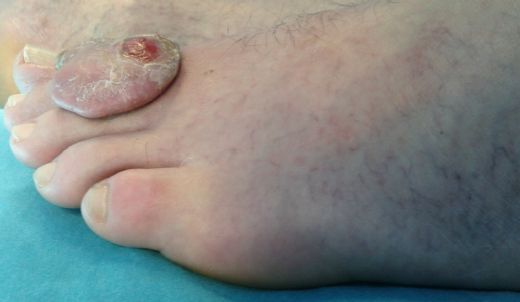

Histopatolojik Sınıflama Histopatolojik sınıflama, tümörlerin mikroskop altında incelemesiyle yapılan bir değerlendirmedir. Bu sınıflama, tümörlerin kaynaklandığı doku tipine göre yapılır ve genellikle şu başlıkları içerir: